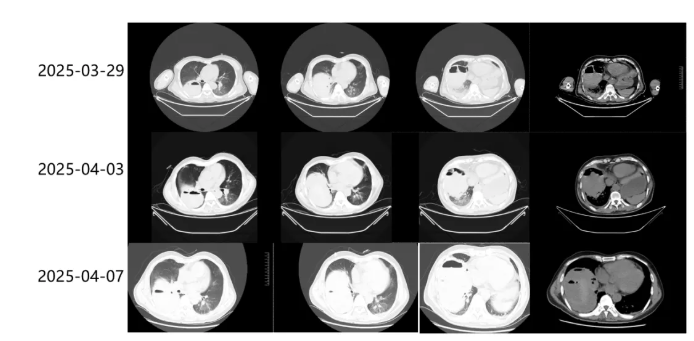

从2025年3月22日凌晨患者开始咯血,至3月24日,患者血红蛋白进行性下降(154g/L降至95g/L),提示活动性出血,3月25日至3月29日血红蛋白未再下降(图9),且患者氧和及意识逐渐好转,于3月26日拔管撤机。连续复查床旁胸片,提示右肺出血未再进展(图10),但3月28日胸片新发右下肺空洞,患者出现咳暗红色脓痰,为了一探究竟,我们在3月29日复查胸部CT。此时,CT显示右肺下叶团片状高密度影,内可见气体影,截面约110mm×97mm,考虑血肿(图11)。每间隔4天连续复查胸部CT,右下肺血肿竟有增大趋势(图11),面对如此巨大血肿,下一步又该如何处理?

患者胸部CT提示肺内巨大血肿,查阅文献,肺内血肿常见于肺挫裂伤,常见处理方式如下:1.少量出血,保守治疗,待血肿自行吸收;2.活动性出血,可考虑介入栓塞出血血管;3.外科手术,肺段或肺叶切除。本患者出血量较大,3-29血红蛋白102g/L,4-3再次下降至86g/L(图9),CT提示血肿体积增大(图11),考虑仍活动性出血。

图11 患者胸部CT

止血方面:1.停用抗凝药,动态监测血红蛋白、咯血量、血氧饱和度变化,预估是否继续出血。2.介入科会诊,可行肺动脉栓塞止血,但患者肺动脉压力高,栓塞肺动脉后可能造成肺动脉压力进一步升高,加重右心衰竭,故暂不考虑介入。停用抗凝药后,患者血红蛋白未再下降,4-7复查胸部CT血肿未再增大。

血肿处理:患者目前血肿稳定,血肿体积过大,压迫肺组织,占据胸腔体积,加重呼吸困难,不适合保守治疗。患者肺动脉压力高,全麻风险高,不建议外科手术治疗。仔细阅读4-7胸部CT,出血部位位于右肺下叶前基底段和外基底段,血肿内液性暗区与气体密度区混杂,影像类似肺脓肿,是否可参考肺脓肿穿刺置管引流原则,引流血肿?反复与外科沟通,方案可行,在血红蛋白稳定后,于4-7行超声引导下行血肿穿刺置管引流,引流出暗红色不凝液体。继续引流3天,共计流出800ml液体,4-10复查胸部CT,血肿明显吸收(图12),血红蛋白无下降、患者呼吸困难较前缓解。但患者D-二聚体明显升高,考虑目前无活动性出血,避免血栓形成,平衡出血与抗凝,予普通肝素抗凝,监测APTT,实时调整肝素用量。